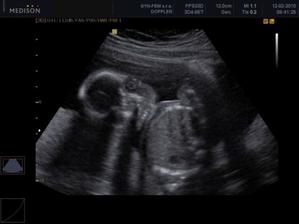

30.12. Jsem se byla zaregistrovat k porodu u Apolináře. ROK 2010 🙂 TO SE BUDOU DÍT VĚCI. 12.1. interní vyšetření + EKG a odběr - všechno OK, 14.1. UTZ žil kvůli natékání nohou (už ráno mám kotníky jako bambule). Výsledek: tromboza nehrozí UF!, nedomýkavost chlopní tepen, pže tělo je víc zatíženo. Doporučeno: nosit těhu punčochy, hodně pít, víc chodit, málo sedět a stát. Pak jsem utíkala na gyn na triplle testy a sestra mě objednala i na velký UTZ kam půjde i manža a budeme mimíska mít na DVD. Jsme oba natěšený! 20.1. UTZ ledvin - vše v pořádku. Tak velký UTZ proběhl OK. Nechceme vědět co to bude tak to stále nevíme 🙂)) . Triplletesty jsou taky v pořádku. 18.2. poradna - tak jsem měla nízký tlak 🙂)) jindy ho mám vysoký tak jsou trošku zmatený. Říkám, že mají blbý tlakoměr. Gynekologicky a miminkovsky všechno dobrý. 21.2. domluveno jméno pro klučíka - TOMÁŠEK .... ještě tu holčičku 😉)).